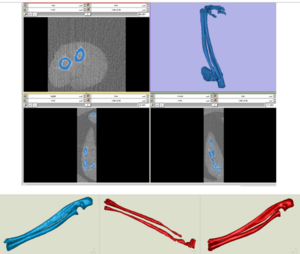

- 9.14 Integration of the Vascular Modeling Toolkit in 3D Slicer